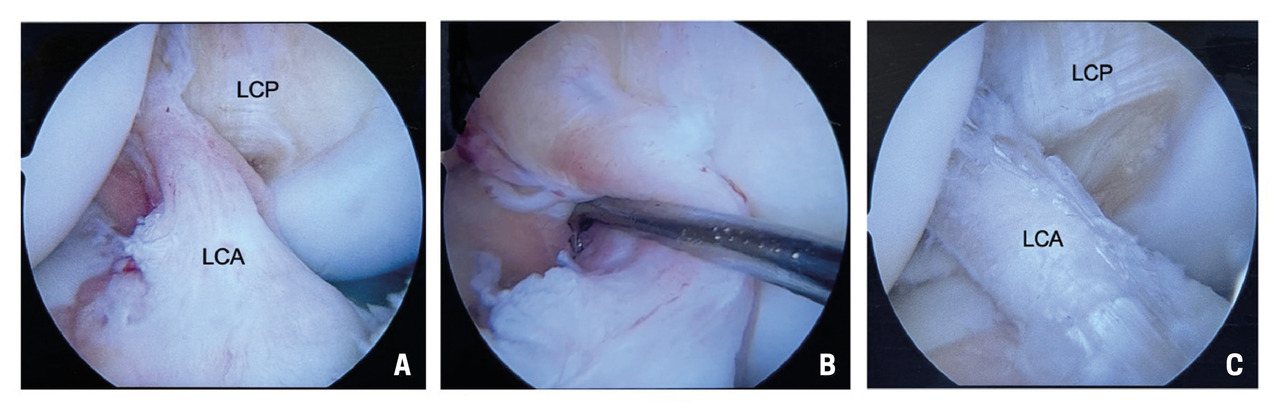

Il existe énormément de controverses au sein de la communauté orthopédique concernant la technique chirurgicale à employer.7 Les deux techniques les plus répandues sont les reconstructions par autogreffe sous arthroscopie, soit au tendon rotulien, soit aux tendons ischio-jambiers (fig. 4). Un renfort latéral est également très souvent effectué pour accroître la stabilité rotatoire du genou, notamment chez le sportif en compétition, en cas de ressaut rotatoire explosif à l’examen clinique ou en cas de rupture itérative. À noter que pour pouvoir envisager une intervention chirurgicale, il est important que le genou soit sec, bien mobile, avec une bonne contractilité du quadriceps. En l’absence de ces conditions, l’intervention expose à un risque de raideur postopératoire, raison pour laquelle des séances de rééducation sont fréquemment prescrites pour préparer le genou à la chirurgie.